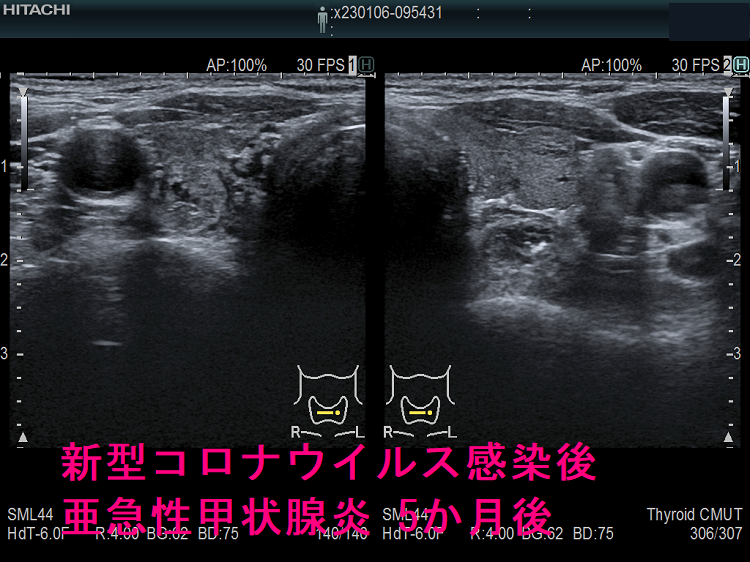

以下は、長崎甲状腺クリニック(大阪)の自験例です。

長崎甲状腺クリニック(大阪)の自験例

急性期

1.5か月後

5か月後